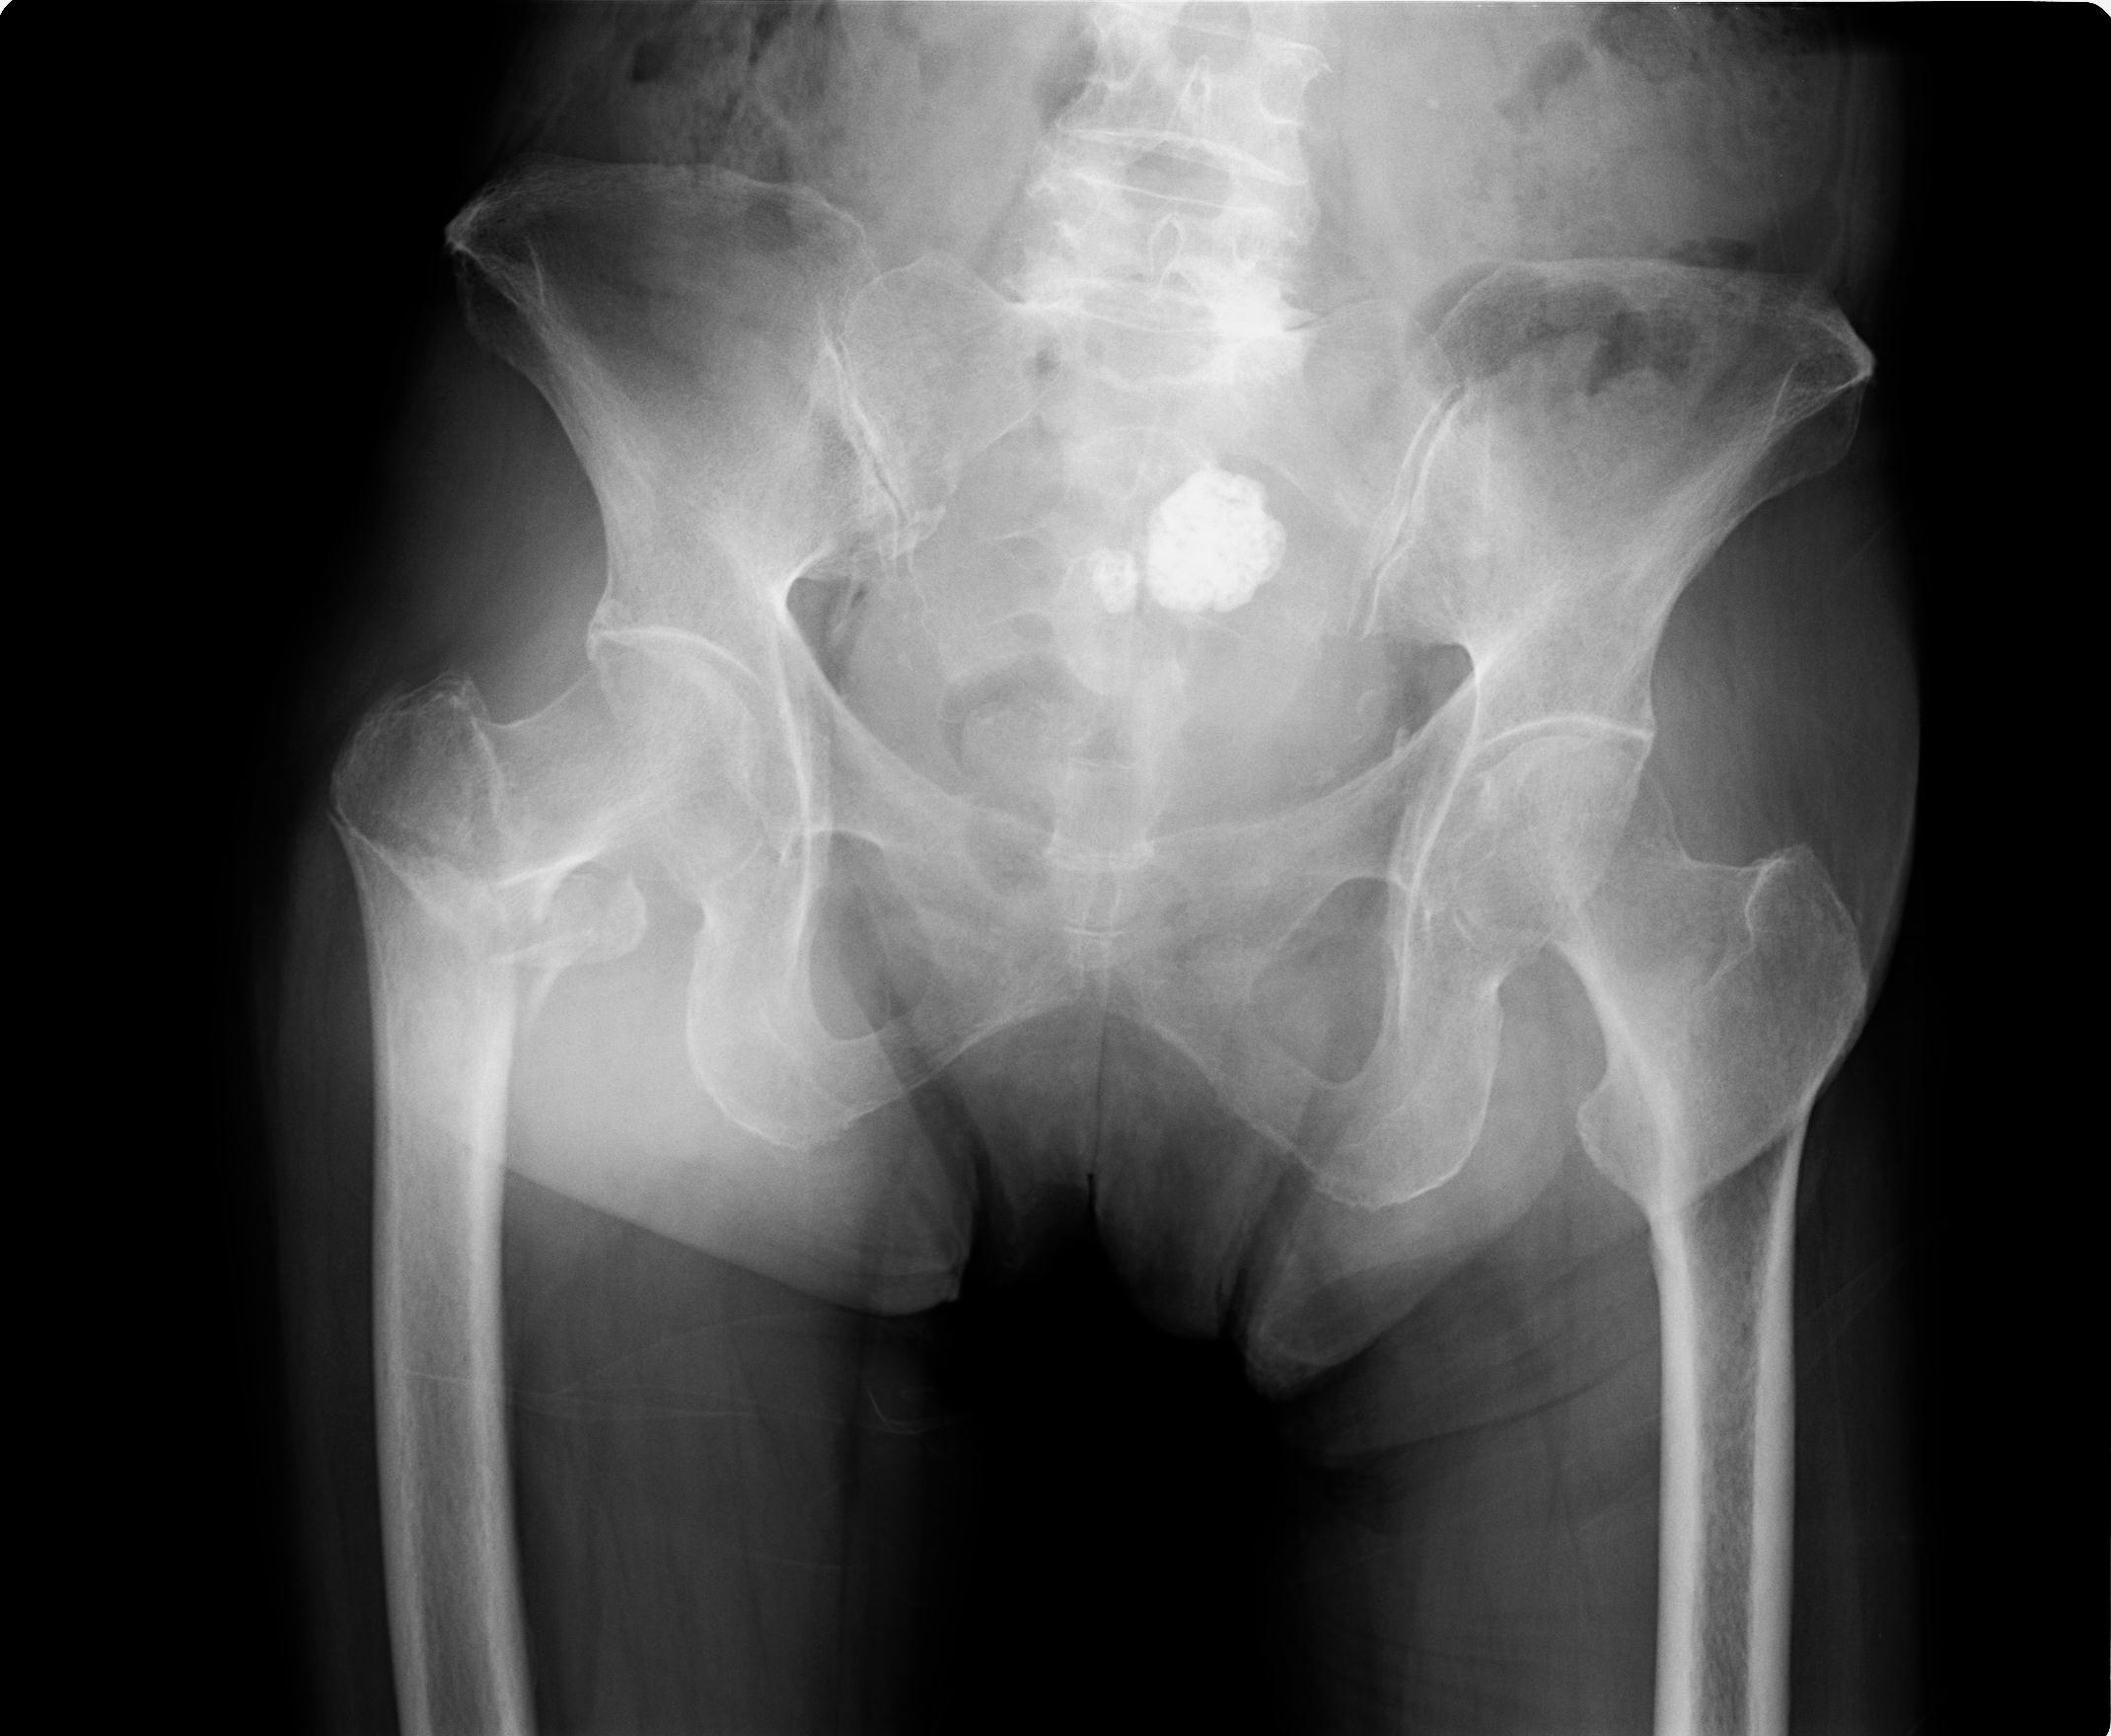

100703 1/27 両股正面+軸 1/29 両股正面+軸 94歳女性 パンソンロン

37 1/18 両股正面+軸 1/22 2R 86歳女性 右転子下

91569 3/25 両股正面とラウエン 70歳女性 人工骨頭+バンクーバー